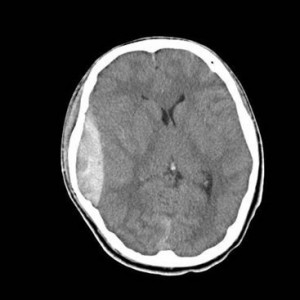

交差点を歩行横断中、後方よりの右折自動車に跳ねられ受傷。診断名は外傷性くも膜下出血、脳挫傷、骨盤骨折となった。

まず、脳神経外科医に最終MRI検査と読影をして頂いた。そこで前頭葉の損傷に注目、家族の観察と受傷部位を結ぶべく、必要な検査を検討した。